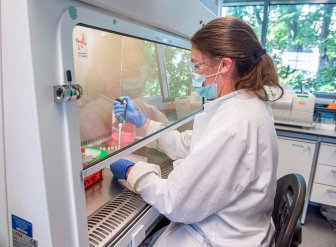

Kelowna included in global study for COVID-19 treatmentsThe Medical Arts Health Research Group is working on treatments for COVID-19 and are hoping to bring new treatments to the Okanagan.HealthMar 26, 2021

What we have learned about treating COVID-19 one year into the pandemicA year into the COVID-19 pandemic, scientists have learned a lot about the virus — and one major area of growth has been learning how best to treat patients who catch the virus.CanadaMar 12, 2021

‘Unpredictable pathogen’: New coronavirus study highlights severity of illnessPneumonia, respiratory problems, kidney failure and sepsis among the most common complications found in a large U.S. study of COVID-19 patients.HealthDec 8, 2020

Almost 1M have died from coronavirus. Their deaths taught researchers about treatmentPatients are already benefiting. Though more deaths are expected this fall because of the recent surge in coronavirus infections in the U.S. and elsewhere, there also are signs that death rates are declining and that people who get the virus now are faring better than did those in the early months of the pandemic.HealthSep 27, 2020

Researchers hope manufactured antibodies could help treat COVID-19Manufactured antibodies, which are used to treat some forms of cancer, could also be used for COVID-19, researchers say.HealthAug 4, 2020

37 countries pledge to share coronavirus research, vaccines and treatmentsA group of developing countries wants to ensure that eventual COVID-19 medicines are available to everyone.HealthMay 29, 2020

Coronavirus: Cuba says 2 drugs have reduced its death tollHealth authorities have reported just two virus-related deaths over the past nine days among more than 200 active cases on the Caribbean's largest island, a sign they may have the worst of the outbreak under control.WorldMay 22, 2020

Remdesivir has emerged as a possible COVID-19 treatment — what happens next?At present, COVID-19 is a disease with no approved treatments or vaccines.CanadaMay 1, 2020